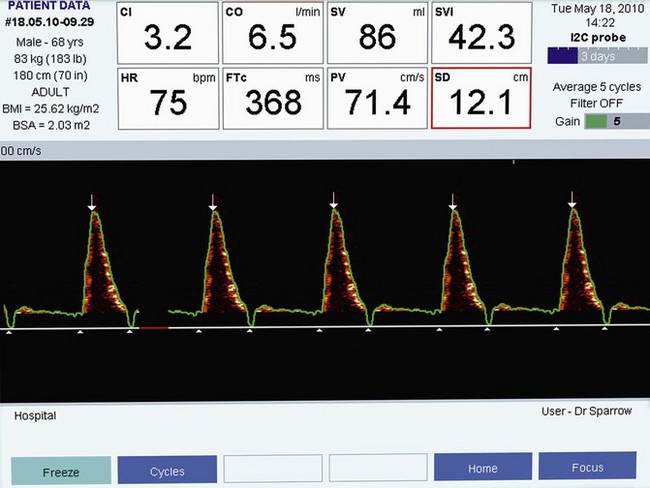

Aortic flow signal

Flow signals acquired by the probe are processed by fast Fourier transformation (FFT) and represented on the monitor as a spectral density display of the distribution of red blood cell flow velocities (vertical axis) against time (horizontal axis). Descending aortic blood flow gives a positive deflection and is approximately triangular in shape (Fig. 16.3).

Figure 16.3 Ideal aortic waveform. The brightness of the signal is on the periphery of the waveform.

Note that flow in the descending aorta occurs predominantly during systole; there is minimal forward flow in diastole. Correct identification of the descending aortic waveform is a prerequisite for oesophageal Doppler monitoring. Ideally, the aortic waveform should appear triangular with the ‘brightness’ confined to the peripheral edge and an absence of signal in the central part of the triangle. This type of waveform is characteristic of a plug flow profile (present in the descending aorta) with a narrow spread of red cell velocities. Turbulent flow or unsatisfactory orientation of the transducer towards the descending aorta would show evidence of spectral dispersion (Fig. 16.4).

Flow time (FT) is the duration of blood flow in the descending aorta resulting from each cardiac ejection. It is indicated by two white triangles at the base of each waveform (Fig. 16.7).